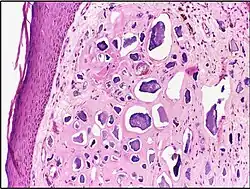

![]() |

Tumor giant cell | Malignant neoplasm showing marked anaplasia. Note the marked nuclear pleomorphism, bizarre cells and tumor giant cells. | Category: Histopathology of giant cell tumors | Giant cell tumor |